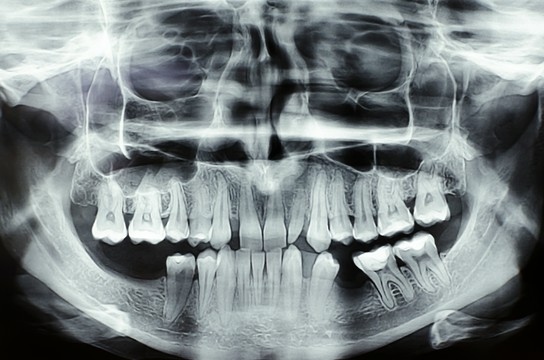

Rentgenodiagnostyka stomatologiczna odgrywa kluczową rolę w precyzyjnej ocenie stanu zdrowia zębów, kości szczęki, żuchwy oraz zatok szczękowych. Dzięki obrazowaniu radiologicznemu możemy wykryć zmiany niewidoczne gołym okiem, takie jak próchnica pod wypełnieniami, ubytki strukturalne, stany zapalne czy torbiele. Zdjęcia rentgenowskie są również niezbędne przy planowaniu leczenia ortodontycznego, implantologicznego oraz chirurgicznego.

W naszym gabinecie wykonujemy różne rodzaje zdjęć RTG, w tym:

• zdjęcia panoramiczne,

• zdjęcia punktowe,

• zdjęcia cefalometryczne.

Nasz sprzęt pozwala nam na uzyskanie obrazów o wysokiej rozdzielczości przy jednoczesnym minimalizowaniu dawki promieniowania. Zdjęcia wykonujemy zarówno w formie analogowej, drukowane na kliszy, jak i w wersji cyfrowej, zapisanej na płycie CD. Dzięki temu pacjenci mogą łatwo przechowywać i udostępniać wyniki badań lekarzom prowadzącym.